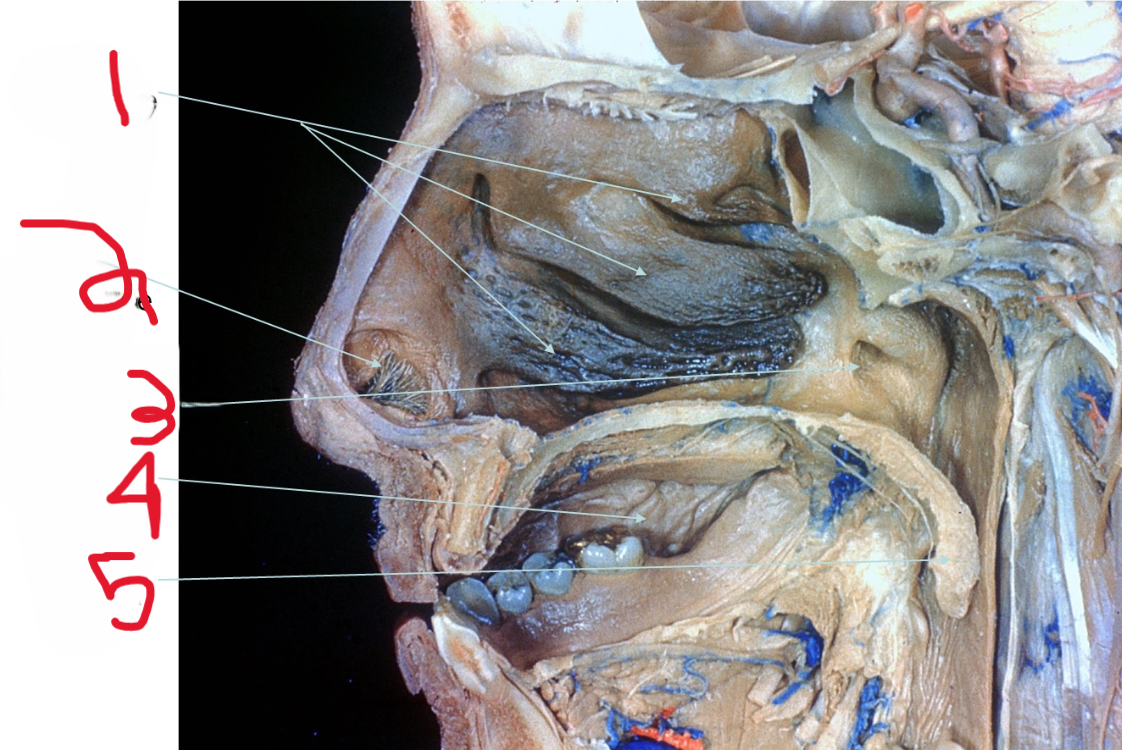

Nasal Conchae

What is depicted by #1

Nasal vestibule

What is depicted by #2

Opening of Pharyngotympanic (auditory) tube

What is depicted by #3

Oral cavity

What is depicted by #4

Uvala

What is depicted by #5